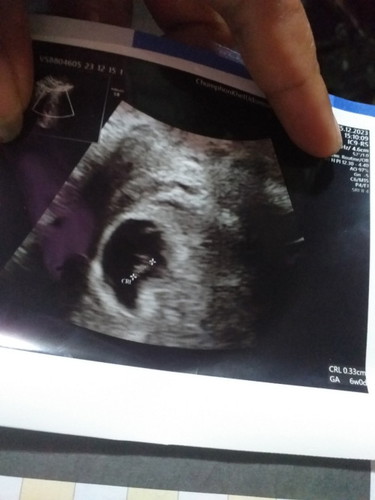

อยากรู้ว่าเด็กในท้องมีตัวแค่ 3 ซม มันกี่เดือนคะ แล้วเป็นอันตรายอะไรไหม

อย่ากังวลมากเกินไปนะคะ ในใบเขาวัดตามขนาดเด็กน้อย 6w ราวๆเดือนนิดๆค่ะ บำรุงดีๆ อย่ายกของหนัก อย่าออกกำลังกายหนัก แล้วก็ไปตามที่หมอนัดนะคะ

ในใบ6w0d ได้6สัปดาห์ค่ะของเราตอน6w1dยังไม่เจอตัวน้องเลยปกติค่ะบ้านนี้เจอน้องตอน8wน้องยาว1.67cm

น้องยังไม่ถึง3ซม.ค่ะแม่อายุครรภ์6วีคก็ประมาณ1เดือนกว่าๆค่ะ

ก็นั่นไงค่ะ ในใบซาวด์ก็บอกอยู่ ตรงGA 6w คือ6สัปดาห์

ในใบอัลตราซาวด์มีบอกค่ะตรงมุม 6w0d